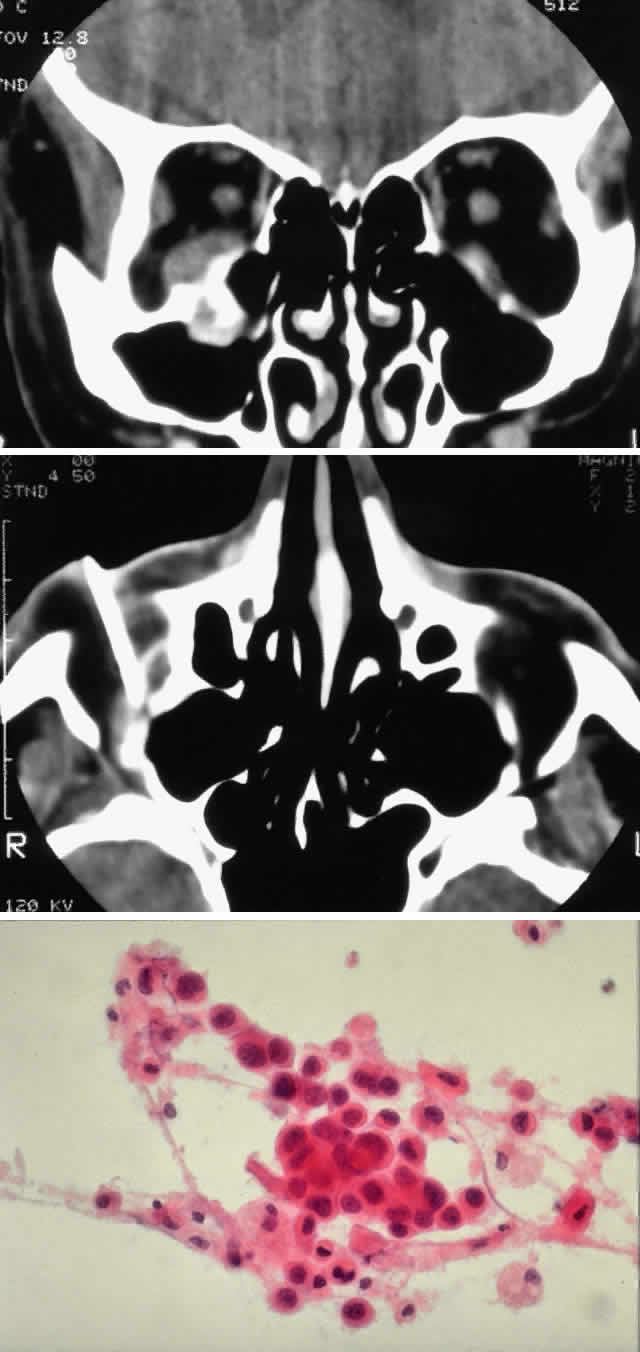

Fig. 3. A 73-year-old man presented with a 2-year history of infraorbital numbness and burning sensation, which had progressed to include the supraorbital region, forehead, and lower face during the past 6 months. He had been treated with radiotherapy for prostate carcinoma 7 months before orbital presentation. Examination was significant for proptosis of 2 mm and dysesthesia, including corneal numbness, in all three divisions of cranial nerve V. CT scan revealed a soft tissue mass in the inferior orbit contiguous with the inferior rectus muscle (A). The lesion extended through the infraorbital canal to involve the pterygopalatine fossa and was associated with soft tissue hanging into the upper portion of the maxillary sinus. An axial CT scan-guided aspiration biopsy was performed (B) and revealed squamous cell carcinoma. Groups of cohesive malignant squamous epithelial cells (C) were noted to have pleomorphic nuclei and abundant eosinophilic to orange cytoplasm, with no features of mucinous differentiation (H & E, × 320). (C from White VA, Rootman J: Orbital pathology. In Albert DM, Jakobiec FA (eds): Principles and Practice of Ophthalmology, Vol 4, p 2342. Philadelphia, WB Saunders, 1994.)

Sebaceous carcinoma has achieved a notorious reputation because it can be difficult to diagnose correctly in the early stages. Clinically, the tumor may masquerade as a chronic chalazion, blepharoconjunctivitis, basal cell carcinoma, keratoconjunctivitis, or very rarely as a primary orbital tumor. Another cause for confusion has been pathologic misdiagnosis of sebaceous carcinoma, most commonly being mistaken for basal cell carcinoma or squamous cell carcinoma. Increasing awareness of the characteristic presentation, along with earlier and more accurate clinical and pathologic diagnosis, has decreased the mortality associated with this tumor. The blepharoconjunctivitis associated with this lesion is the result of intraepithelial (pagetoid) spread of sebaceous carcinoma. The usual clinical appearance is a thickening of the conjunctiva associated with frank injection in areas of invasion (Fig. 9). A careful biomicroscopic examination reveals yellowish, plaque-like foci within the affected epithelium.

Fig. 9. A 79-year-old man had been treated for several years for chronic blepharoconjunctivitis. On examination, he had thickening of upper and lower lid margins, diffuse symblepharon, conjunctival thickening, injection, and yellowish plaque-like foci (A). Conjunctival biopsy confirmed invasive sebaceous cell carcinoma, and subtotal exenteration was performed. Tumor invasion along the globe (B) (H & E, × 32) and into muscle (C) (H & E, × 80) was noted.

The incidence of orbital extension varies from 6% to 35% in large series64–66 and is associated with a 70% mortality rate. These tumors have a propensity to spread to the lymphatic system and subsequently to the lung, liver, brain, or skull. Those that extend into the orbit have approximately a 70% association with preauricular, cervical, or submaxillary adenopathy compared with an overall incidence of approximately 19% for all sebaceous gland carcinomas of the lid and adnexa.

The pathologic diagnosis is based on evidence of sebaceous origin. These carcinomas are usually lobular or consist of cords of cells with a varying degree of sebaceous differentiation and infiltration. The degree of differentiation tends to progress from the periphery toward the center of lobules, mimicking the normal pattern of sebaceous glands. Cells that are differentiated have a foamy or vacuolated, slightly basophilic cytoplasm. In contrast, the less differentiated tumors have cells that are more deeply basophilic and anaplastic, and they display more mitotic figures. The peripheral location of the basophilic, less vacuolated cells produces a pattern similar to basal cell carcinoma, but the cells are more anaplastic. Sebaceous carcinomas have a propensity toward pagetoid spread, invading the basal layers of skin and mucous membranes in a radial fashion. These tumors characteristically contain fat; thus, frozen sections and fat stains are useful in diagnosis and at the time of controlled resection.